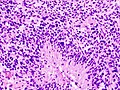

Images

Glioblastoma:

Anaplastic astrocytoma: